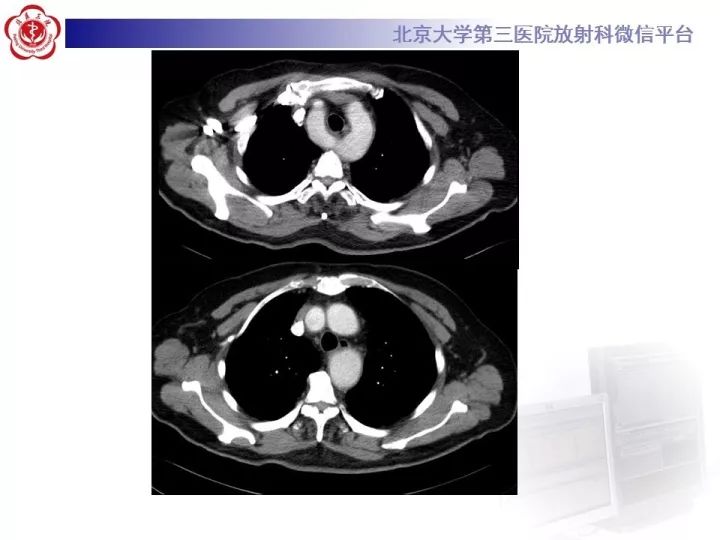

【病例】双主动脉弓畸形1例CT